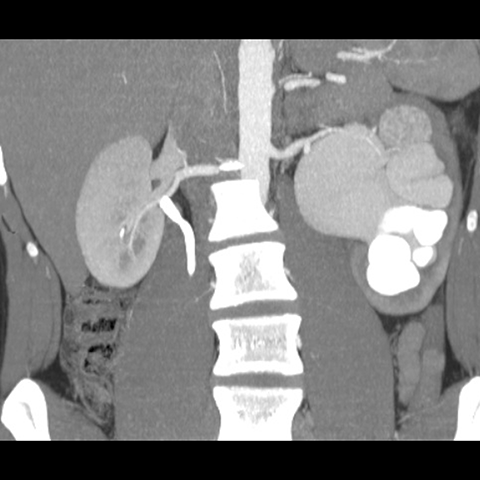

Hydronephrotic kidney [4 of 4]